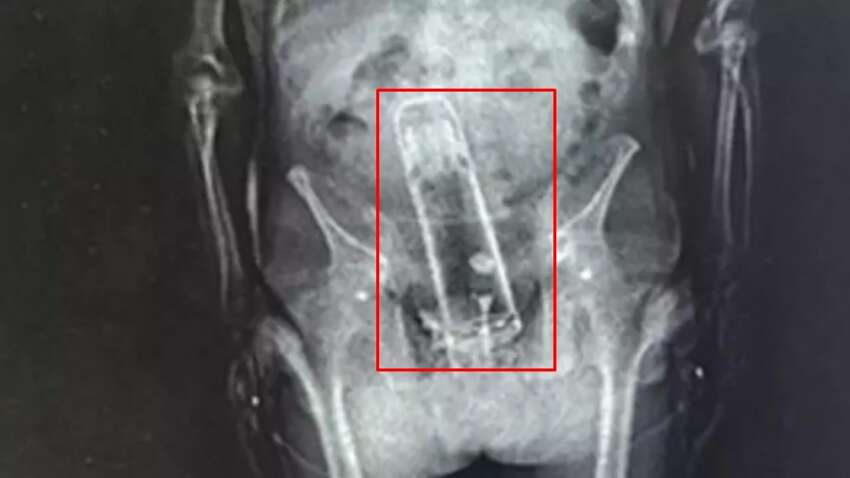

Мужчина засунул термос в задний проход. Фото из открытых источников

По данным американских СМИ, правоохранители задержали мужчину после сообщения об обнаженном мужчине в туалете одного из парков. Впоследствии его арестовали за незаконное проникновение на железнодорожный путь. Когда Фраймайра доставили в тюрьму, во время стандартного рентгеновского осмотра офицеры совершили неожиданное открытие. В его прямой кишке находился термос.

Мужчина спрятал термос в неожиданном месте

Медики в больнице сумели безопасно удалить термос из тела мужчины. По словам шерифа, это могло спасти ему жизнь, ведь подобные предметы могут вызвать разрывы и внутренние кровотечения.